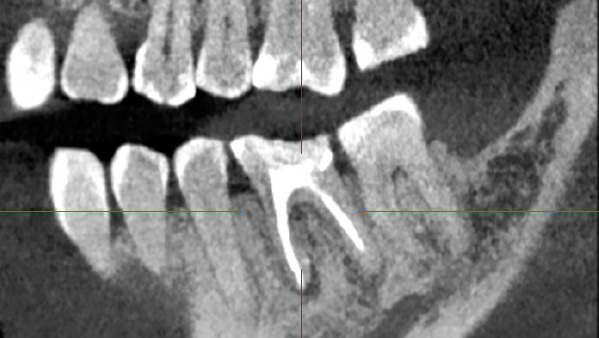

Через год мы сделали повторную компьютерную томографию и увидели положительный результат. Очаг инфекции ликвидирован, а кость в этом месте отлично восстановилась.

Далее такой зуб в обязательном порядке покрывается коронкой, поэтому пациент направлен к ортопеду для продолжения лечения.